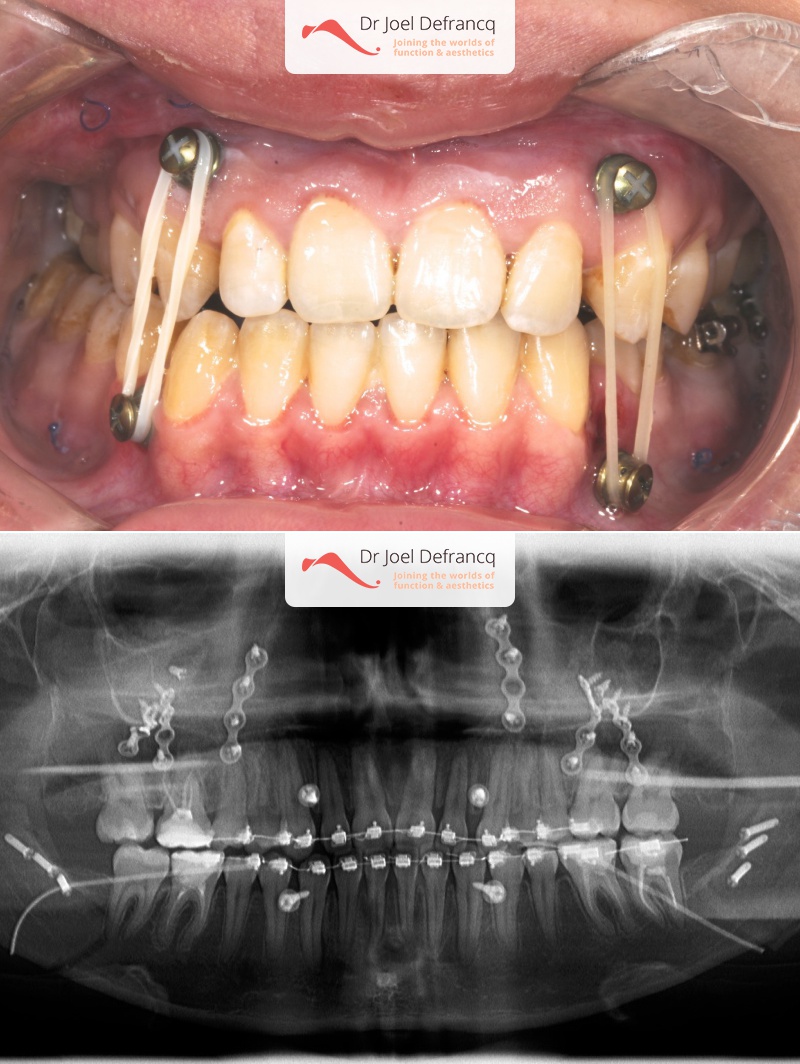

Banja: Scheve kaak , te kleine en te smalle bovenkaak

- Te grote onderkaak (Onderbeet)

- Te kleine bovenkaak

- Asymmetrisch gezicht

- Klasse III

- Verlenging bovenkaak (Le Fort I)

- Onderkaak rotatie

- Posterieure intrusie van de bovenkaak